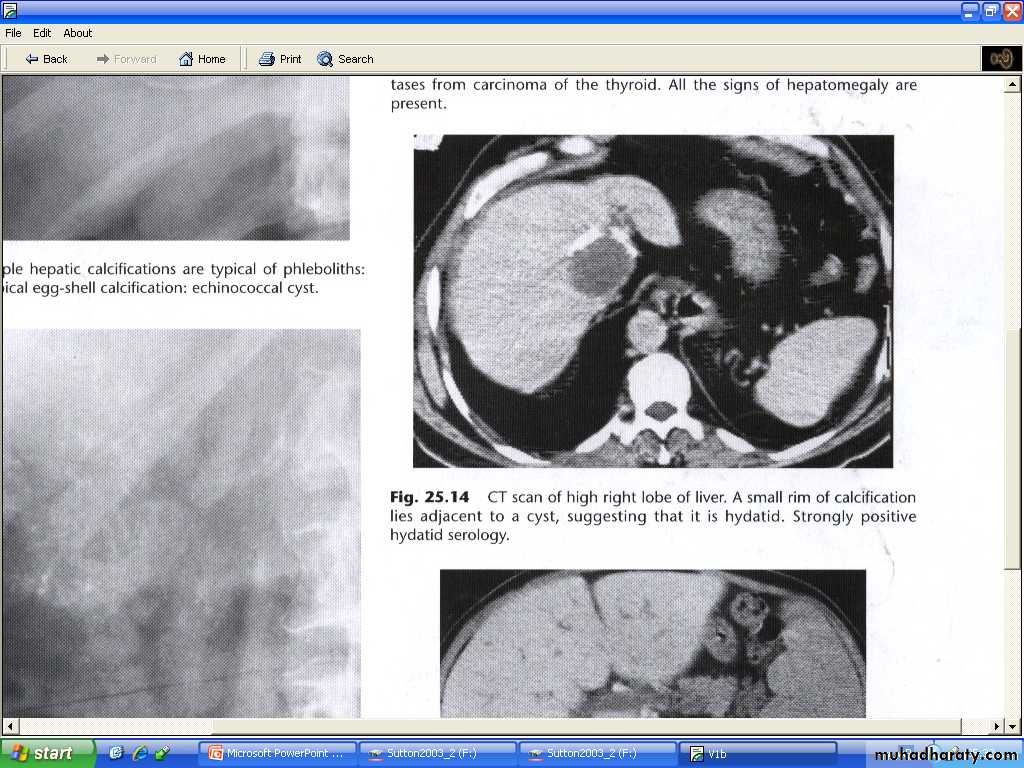

Hydatid cysts:

# may be single or multiple# some shows calcific wall, some shows daughter cysts and some shows internal undulating membrane (waterlily sign )

# unless these features are present ( some time H.cyst resemble simple cyst criteria), H cysts may prove indistinguishable from simple cysts at both US and CT